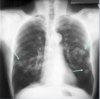

112

What are the two arrows indicating in this CXR?

* Tuberculosis (stretched out cotton ball appearance)

113